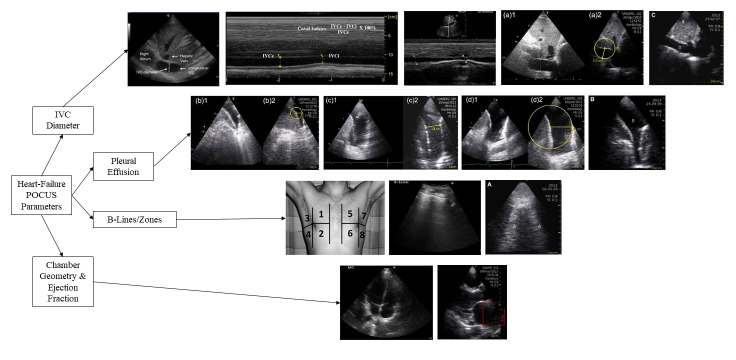

Background: Cardiac point of care ultrasound (POCUS) has shown increasing utility as a tool for diagnosing and managing heart failure (HF). Within cardiology, intravascular volume assessment leveraging visualization of the inferior vena cava (IVC) is a central aspect of care, as IVC size correlates with central venous pressure. This targeted literature review aimed to examine the existing literature assessing the use of POCUS in diagnosis and management of HF patients utilizing POCUS-based IVC measurement either alone or in combination with secondary methods.

Results: The initial search using both PubMed and Ovid resulted in 370 journal publications. After exclusion criteria were used 15 studies were included in the review. Studies were grouped into three categories: 1) how well POCUS was able to identify HF, 2) whether POCUS-based findings correlated with other measures evaluating HF and was able to predict the effect of diuretic administration, and 3) whether POCUS-based findings served as a good prognostic indicator. The 5 studies that evaluated HF identification with POCUS found that both diagnostic sensitivity and specificity may reach 90%-100% when IVC measurement was coupled with a lung ultrasound assessing the presence of B-lines or pleural effusion. Five studies assessing POCUS findings correlating with other HF measures and diuretic effect found that IVC diameter changed significantly with diuretic administration (p<0.05). All 6 studies assessing POCUS as a predictor of long-term mortality or hospital readmission found measures that achieved statistical significance with p<0.05.

Conclusions: Including POCUS as standard-of-care - both as a diagnostic tool in the emergency department and a management tool in in-patient and out-patient facilities - may improve the treatment of HF.